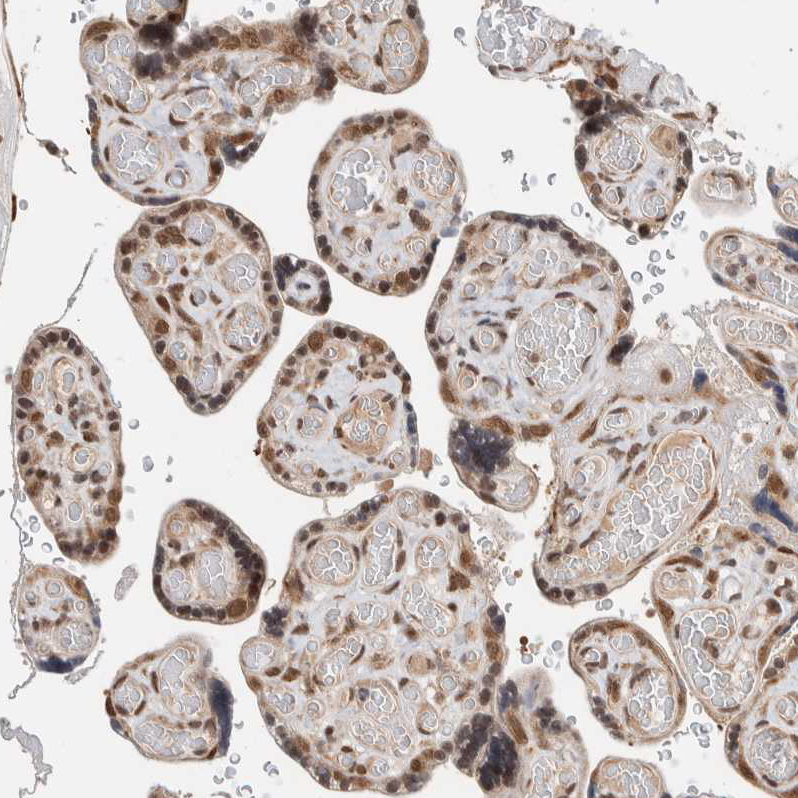

Immunohistochemical staining of human placenta shows moderate nuclear and cytoplasmic positivity in trophoblastic cells.